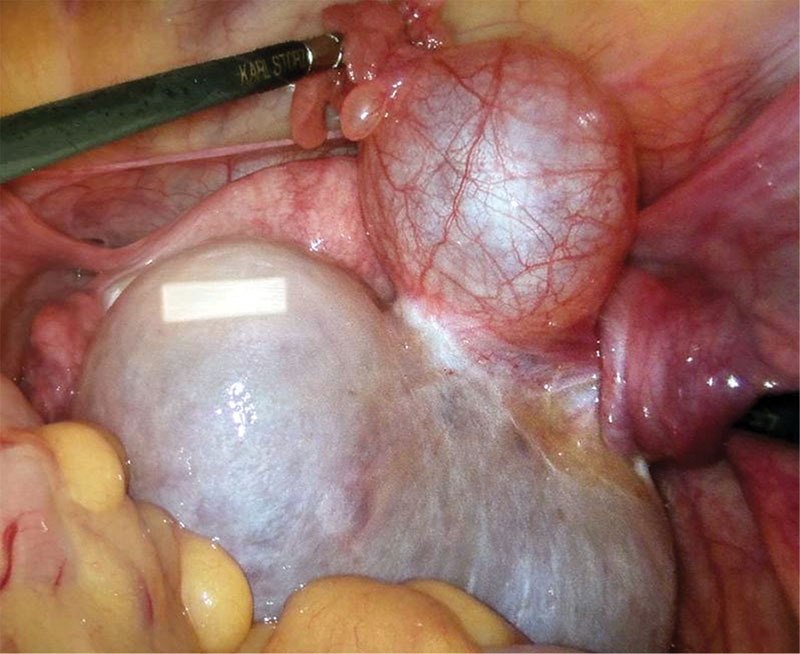

Рис. 1. УЗИ ОМТ пациентки А., 11 лет: объемное образование левых придатков матки, старый перекрут левых придатков матки

При пальпации в области живота – болезненность над лоном слева и опухолевидное образование. Данные ультразвукового исследования (УЗИ): образование в проекции левого яичника размером 4,7 × 3,8 × 4,8 см с неоднородной структурой и четкими контурами, старый перекрут левых придатков матки (рис. 1). Выявлено также небольшое количество свободной жидкости в полости малого таза (0,8 см). Заключение: эхопризнаки образования левого яичника, предположительно кисты желтого тела.